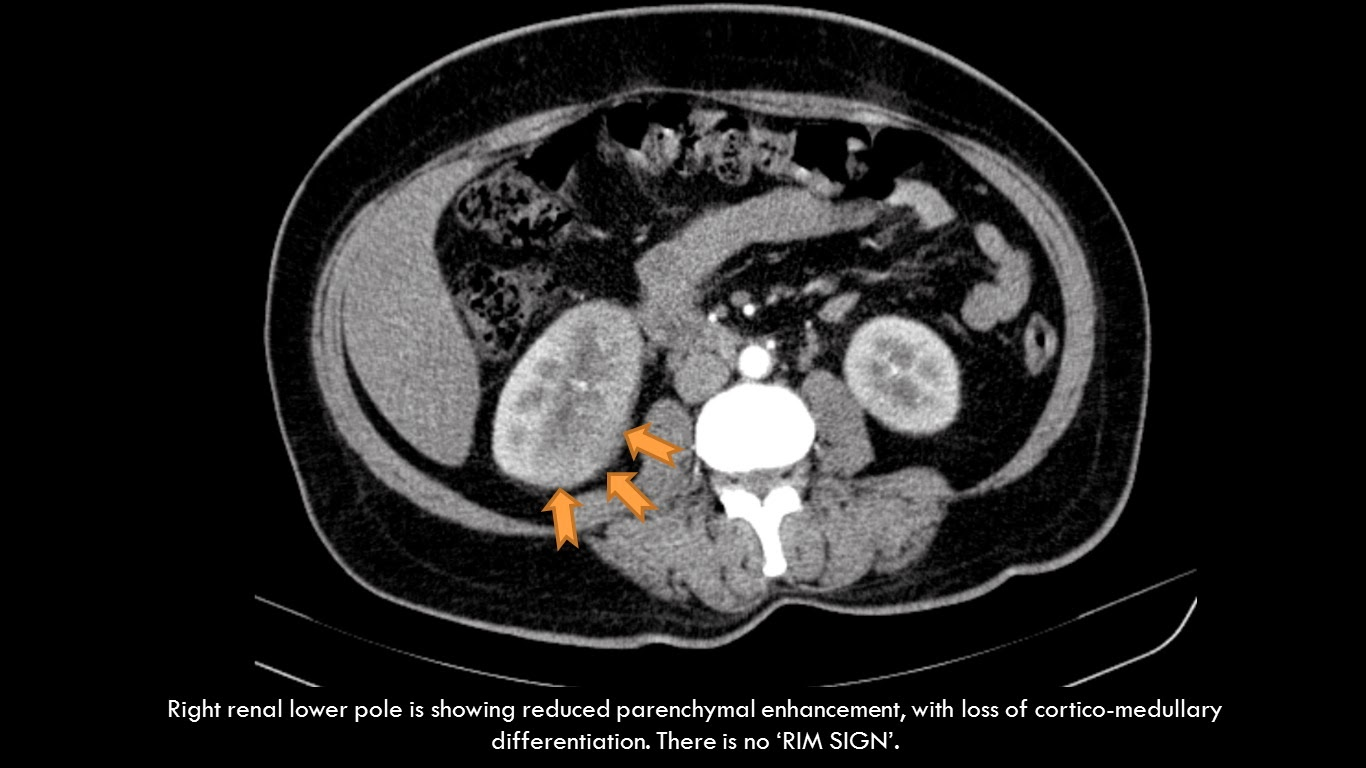

74. 病人主訴發燒和右側腰部疼痛,電腦斷層檢查呈現如圖,下列那一項有關右側腎臟的診斷最 正確?

(A)acute pyelonephritis

(B)renal cell carcinoma

(C)angiomyolipoma

(D)hydronephrosis